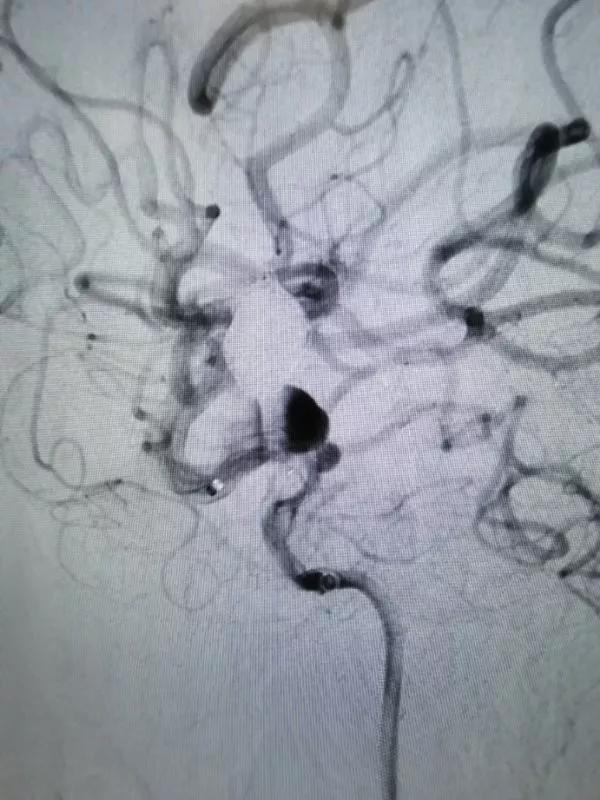

再行右侧颈内动脉血流导向装置置入术:将8F Envoy导引导管置入右侧颈总动脉,105cm 6F Navien导引导管头端置入颈内动脉岩骨段,造影见海绵窦段3个动脉瘤,由近及远直径一次为5mm、8mm、9mm,颈内动脉床突上段可见一大小约为5×4mm的宽颈动脉瘤。

DSA图像